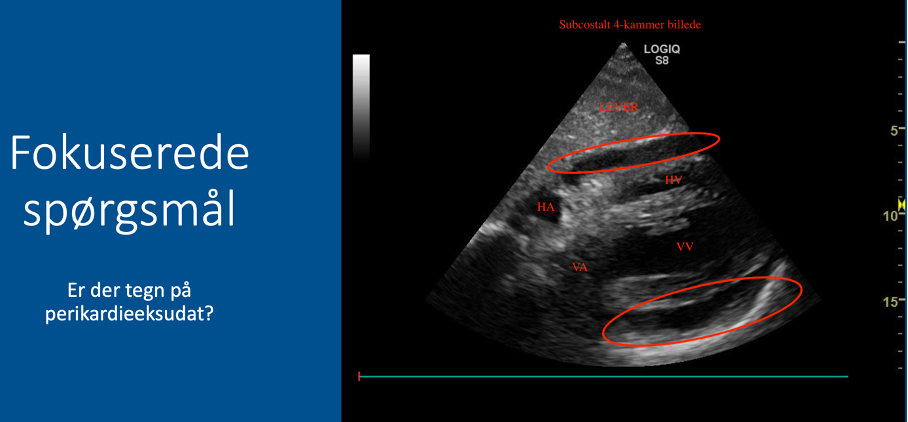

Q

Fokuserede spørgsmål (FHUS):

* Perikardieeffusion: ja/nej?